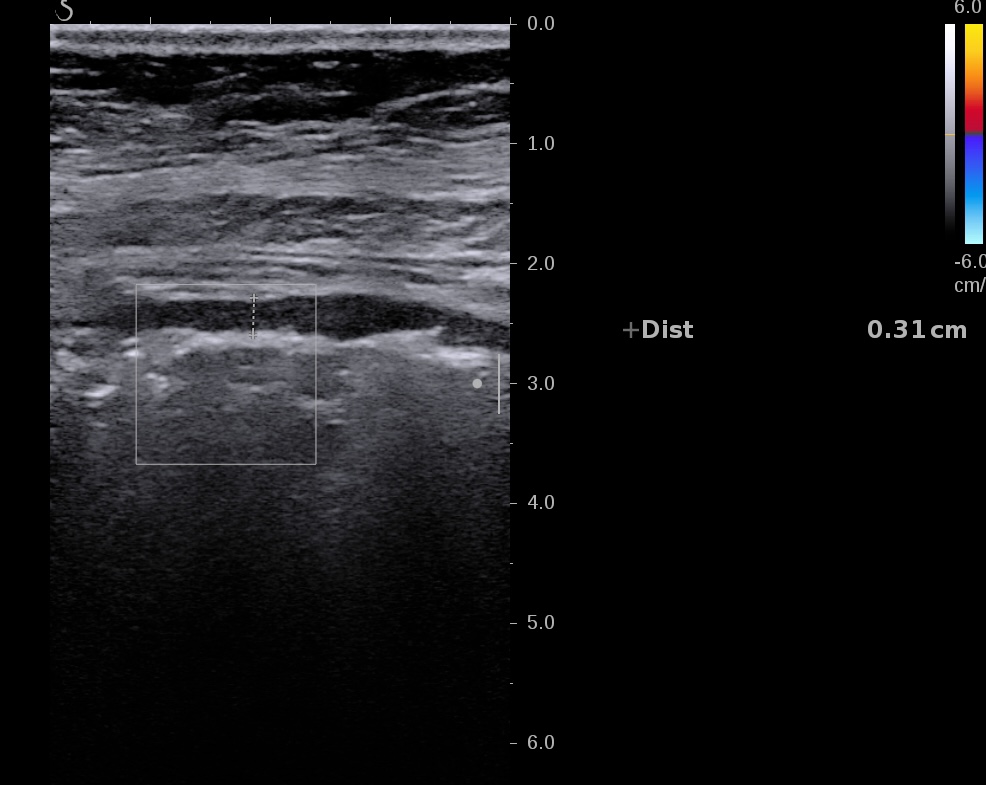

Echographie 22/12/2022

Epaississement considérable par endroit (10 ou 11 mm), disparition totale de la structure en couches, déformation de la surface avec ulcérations, déformation des contours, infiltration de la graisse, hyperactivité Doppler

Le Score de Milan (MUC) est à 17.4

Les images échographiques correspondent parfaitement aux images endoscopiques, et sont finalement beaucoup plus précises que les images scanographiques.